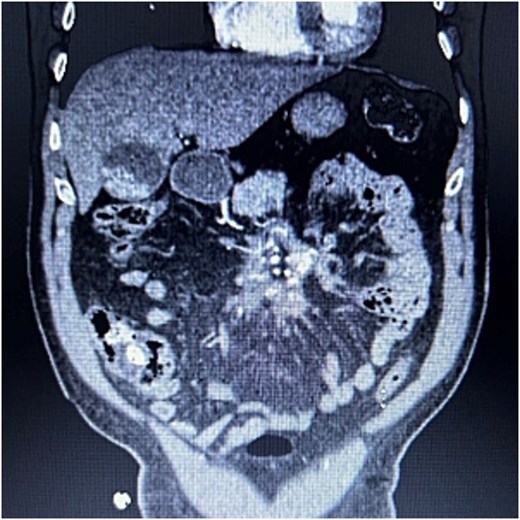

A 83-year-old male presented to his primary care physician with a 6-week history of vague postprandial abdominal pain with associated diarrhea and a 5-lb weight loss. CT abdomen/pelvis showed a 7 × 5 cm spiculated mass at the root of the mesentery involving the superior mesenteric vein and multiple mesenteric arterial branches, and associated small bowel edema and thickening (Fig. 1). He was referred to a surgical oncologist. Tumors markers including CEA, CA 19–9, Chromogranin A, serum serotonin, and urinary 5-HIAA were unremarkable. Octreotide scan showed mild central uptake at the location of the mesenteric mass (Fig. 2). Diagnostic laparoscopy showed mesenteric mass at the root of the mesentery and biopsy revealed fibrous tissue with calcifications and no evidence of malignancy. He was referred to a medical oncologist and began Lanreotide injections for presumed neuroendocrine tumor. He completed 12-months of Lanreotide therapy, however he remained symptomatic with abdominal pain, diarrhea, and ongoing weight loss. He was referred to a tertiary cancer center, but no treatment was offered in the absence of proven malignancy. He then saw another surgeon who obtained a Ga-DOTATATE PET CT scan which showed moderate ascites, an increase in size of the mesenteric mass to 7.3 × 6.3 cm, low level of tracer at the periphery of the mass, and intense activity within the 2nd and 3rd portions of the duodenum. He was referred to an advanced endoscopist for EGD/EUS, which did not show a duodenal mass. Due to ongoing symptoms he was scheduled for repeat diagnostic laparoscopy with possible resection of mesenteric mass versus repeat biopsy. On the morning of surgery, he presented with dizziness and acutely worsening abdominal pain. He was tachycardic and hypotensive with abdominal distention and peritonitis on exam. Due to concern for a perforated viscus the decision was made to proceed with exploratory laparotomy. He was found to have purulent ascites and dusky small bowel with edema and central swirling atop a large, calcified mesenteric mass. Upon further inspection, a single site of small bowel perforation was identified and there was leakage of succus into the abdominal cavity. A palliative resection of the perforated small bowel and adjacent mesenteric mass was performed. 100 cm of small bowel was resected en bloc with the mesenteric mass, but residual gross tumor was left at the base of the superior mesenteric artery and encasing the middle colic artery (Fig. 3). Intra-operative doppler and Firefly were used to determine perfusion of the remaining 120 cm of small bowel and a side-to-side small bowel anastomosis was performed. He was hemodynamically stable at the termination of the procedure, extubated, and admitted to the intensive care unit for close observation. Post-operatively, he converted into atrial fibrillation with rapid ventricular response and ultimately died from cardiac arrest secondary to a massive myocardial infarction. Pathology was significant for sclerosing mesenteritis without evidence of malignancy.

Anterior–posterior view of CT abdomen/pelvis scan showing large, central calcified mesenteric mass, Case 1.